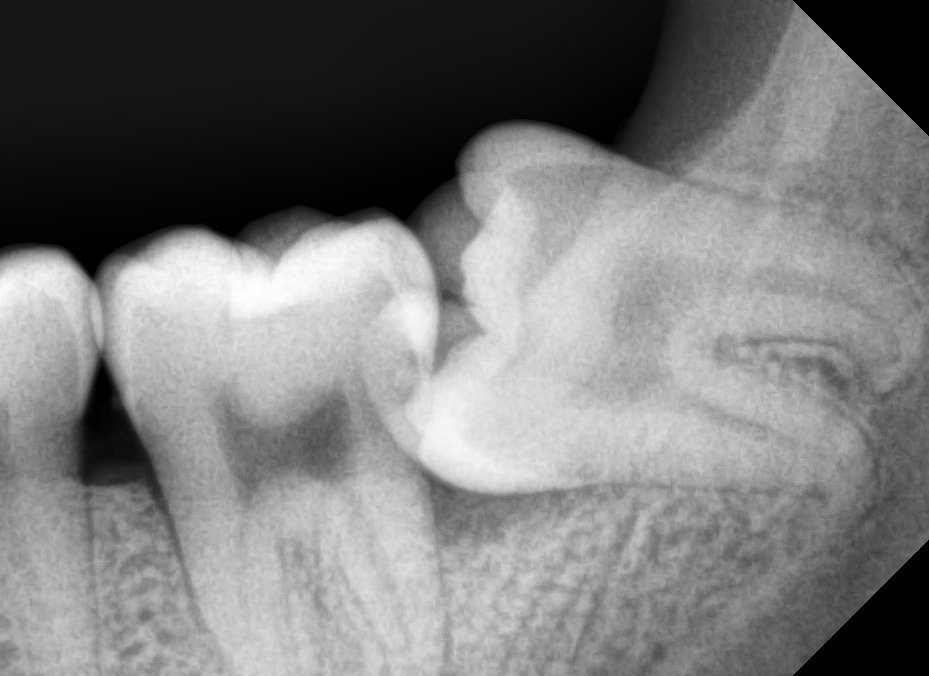

Odontektomi adalah prosedur bedah gigi untuk mengangkat gigi yang sulit dicabut dengan metode biasa. Dokter gigi biasanya melakukan tindakan ini pada gigi dengan impaksi, yaitu gigi yang tumbuh sebagian atau sepenuhnya terpendam di dalam gusi maupun tulang rahang.

Kasus paling sering yang membutuhkan odontektomi terjadi pada gigi bungsu (molar tiga). Gigi bungsu yang tumbuh miring atau kekurangan ruang di rahang sering menimbulkan nyeri, infeksi, serta gangguan pada gigi sebelahnya.

• Gigi bungsu impaksi, tumbuh tidak sempurna dan menekan gigi di sebelahnya.

• Kerusakan gigi sebelahnya akibat dorongan dari gigi bungsu.